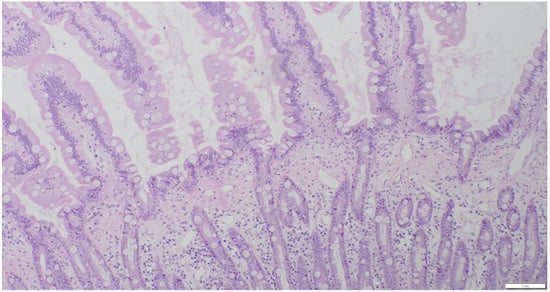

2.3. Sample Collection and Histopathologic Assessment

3.2. Results of Histology/IHC and Clonality Testing